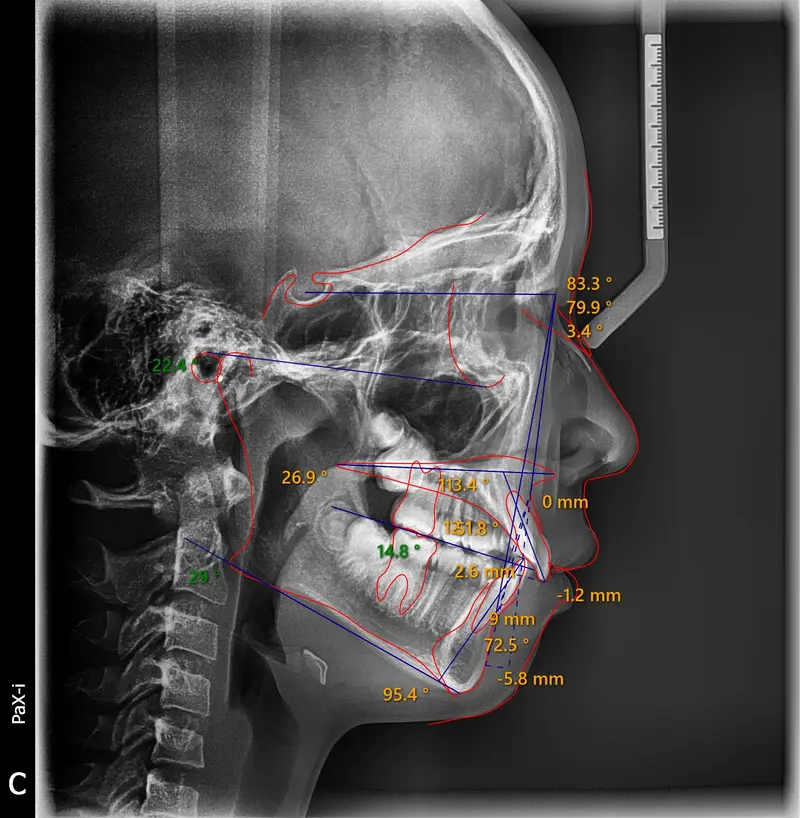

The Diagnosis

Deep bite with over-erupted upper central incisors. The patient presented with a "Gummy Smile" and uneven gingival margins, where the front teeth sat too low relative to the upper lip.

The Engineering

We utilized Temporary Anchorage Devices (TADs) to apply pure intrusive forces. By anchoring to the bone, we lifted the anterior teeth and gum line upwards (Intrusion) to reduce the gummy display and level the smile arc without jaw surgery.